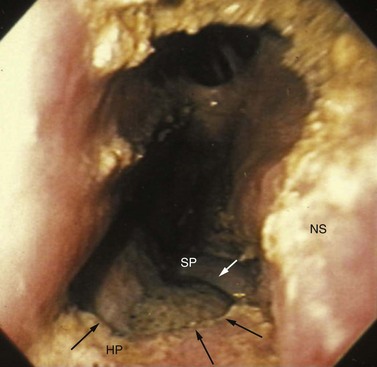

Complications associated with extracting a cheek tooth by repulsion